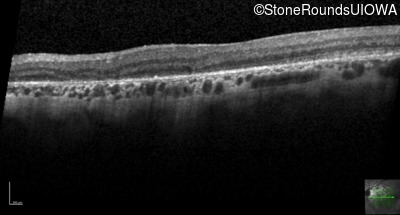

Age at visit: 57 years